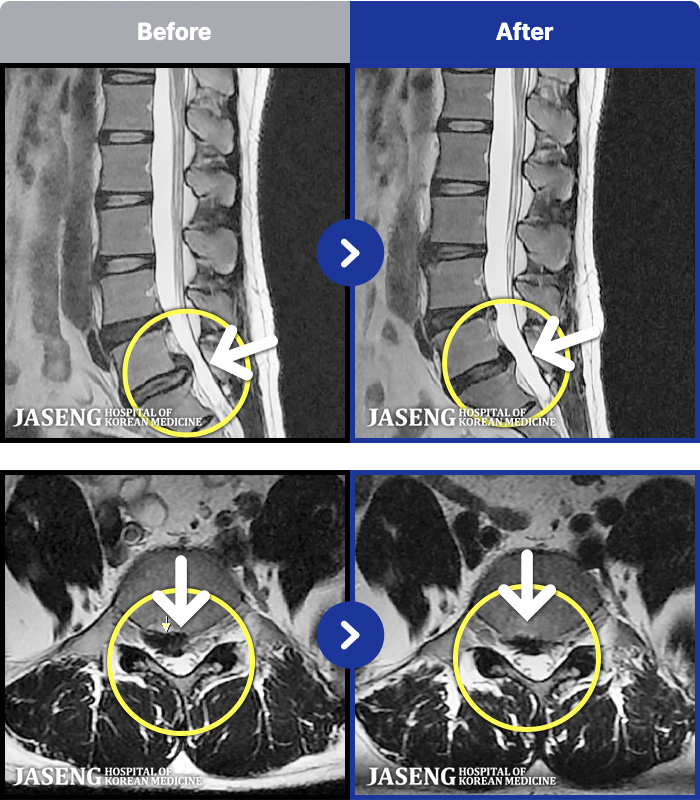

[Կñ:20.10.14~24.10.07]

[_㸮ũ] ġ . Ƹ, ߹ٴ

No.44

ȸ 125

2024.12.24